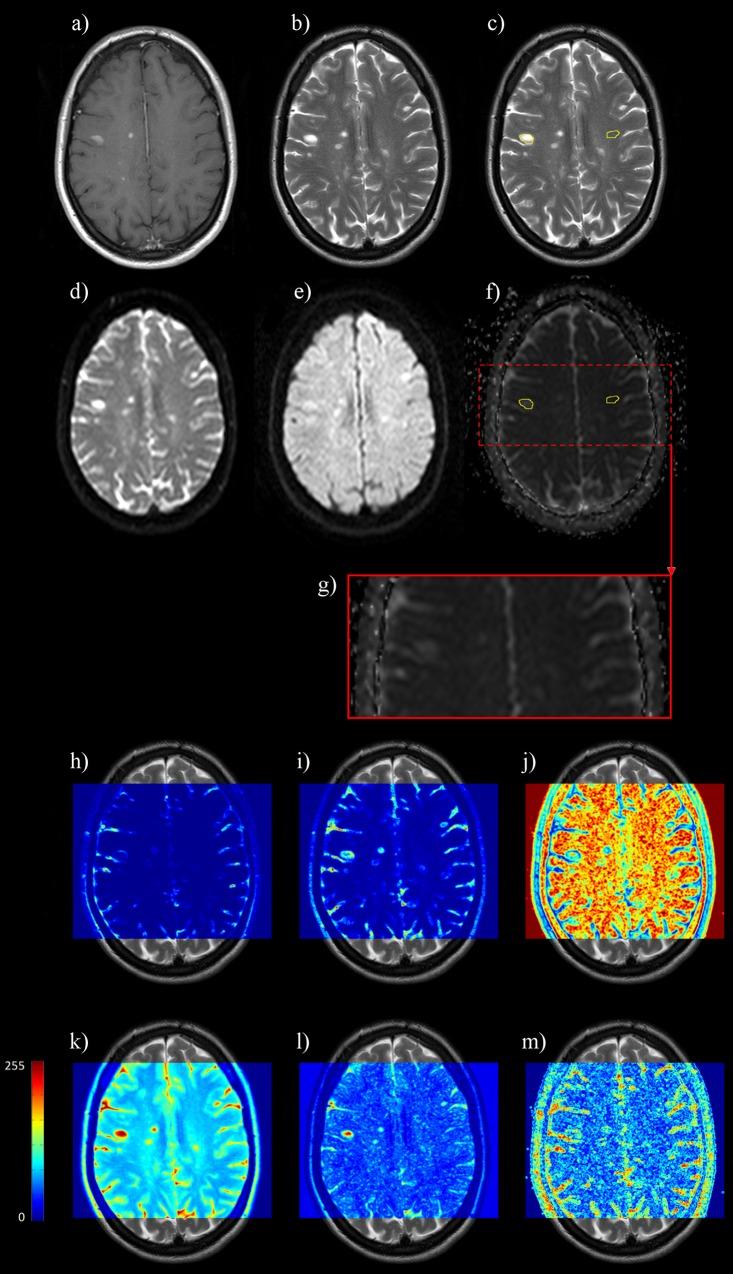

Brain blood barrier breakdown as assessed by contrast-enhanced (CE) T1-weighted MR imaging is currently the standard radiological marker of inflammatory activity in multiple sclerosis (MS) patients. Our objective was to evaluate the performance of an alternative model assessing the inflammatory activity of MS lesions by texture analysis of T2-weighted MR images. Twenty-one patients with definite MS were examined on the same 3.0T MR system by T2-weighted, FLAIR, diffusion-weighted and CE-T1 sequences. Lesions and mirrored contralateral areas within the normal appearing white matter (NAWM) were characterized by texture parameters computed from the gray level co-occurrence and run length matrices, and by the apparent diffusion coefficient (ADC). Statistical differences between MS lesions and NAWM were analyzed. ROC analysis and leave-one-out cross-validation were performed to evaluate the performance of individual parameters, and multi-parametric models using linear discriminant analysis (LDA), partial least squares (PLS) and logistic regression (LR) in the identification of CE lesions. ADC and all but one texture parameter were significantly different within white matter lesions compared to within NAWM (p < 0.0167). Using LDA, an 8-texture parameter model identified CE lesions with a sensitivity Se = 70% and a specificity Sp = 76%. Using LR, a 10-texture parameter model performed better with Se = 86% / Sp = 84%. Using PLS, a 6-texture parameter model achieved the highest accuracy with Se = 88% / Sp = 81%. Texture parameter from T2-weighted images can assess brain inflammatory activity with sufficient accuracy to be considered as a potential alternative to enhancement on CE T1-weighted images.

通过对比增强(CE)T1加权磁共振成像评估的脑血脑屏障破坏是目前多发性硬化症(MS)患者炎症活动的标准放射学标志物。我们的目的是评估一种通过T2加权磁共振图像纹理分析评估MS病变炎症活动的替代模型的性能。21例确诊为MS的患者在同一台3.0T磁共振系统上接受了T2加权、液体衰减反转恢复(FLAIR)、扩散加权和CE-T1序列检查。从灰度共生矩阵和游程长度矩阵计算得到的纹理参数以及表观扩散系数(ADC)对正常白质(NAWM)内的病变和镜像对侧区域进行了特征描述。分析了MS病变与NAWM之间的统计学差异。进行了ROC分析和留一法交叉验证,以评估各个参数的性能,以及使用线性判别分析(LDA)、偏最小二乘法(PLS)和逻辑回归(LR)的多参数模型在识别CE病变中的性能。与NAWM相比,白质病变内的ADC和除一个纹理参数外的所有纹理参数均有显著差异(p < 0.0167)。使用LDA,一个8纹理参数模型识别CE病变的灵敏度Se = 70%,特异性Sp = 76%。使用LR,一个10纹理参数模型表现更好,Se = 86% / Sp = 84%。使用PLS,一个6纹理参数模型的准确率最高,Se = 88% / Sp = 81%。T2加权图像的纹理参数能够以足够的准确性评估脑炎症活动,可被视为CE T1加权图像增强的潜在替代方法。